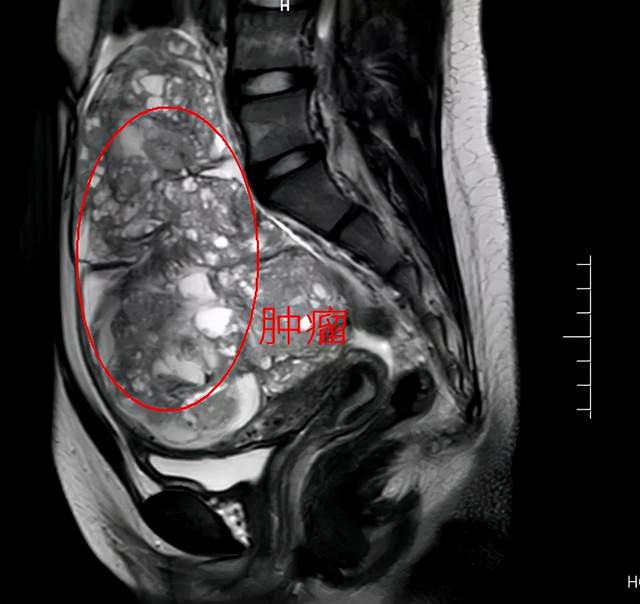

巨大卵巢肿瘤1例.